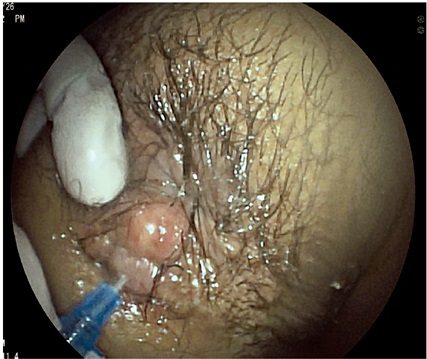

Los pacientes fueron evaluados en posición de decúbito lateral izquierdo, luego de esto se realizó inspección perianal detallada, tacto rectal y evaluación endoscópica hasta el recto superior; se procedió a la evaluación endosonográfica localizando como estructura anatómica guía en nivel anterior el útero (o vejiga cuando el útero estaba ausente) en la mujer, o la próstata (uretra masculina cuando la próstata estaba ausente) en el hombre, además de la localización del músculo puborrectal en nivel posterior para ambos. La izquierda fue localizada a las 3 del reloj y la derecha a las 9 del reloj. En caso de evaluación de lesiones tipo masa, se utilizó agua como medio acústico; asimismo, en casos donde se estudió fístula perianal, se insertó una cánula en el orificio secundario perianal con la porción no punzante de un catéter 18 o 20 G, se inyectó agua oxigenada para generar un efecto de contraste a través del trayecto fistuloso y para que fuera visible endosonográficamente en toda su extensión. Se realizó medición del grosor de los esfínteres a las 3 o 9 del reloj, medición de las masas, y se aplicó el sistema internacional TNM de estadificación tumoral actualizado para tumores de recto y ano. Para la medición del cuerpo perineal femenino, se realizó tacto vaginal simultáneo y se tomó la medida desde la visión del dedo enguantado visto hiperecogénico hasta la mucosa.

Por otro lado, en el grupo masculino con estudio por incontinencia, el diagnóstico en todos fue cambios por atrofia del aparato esfinteriano, que pudo verse en cualquiera de las localizaciones del canal anal y que se evidenció como engrosamiento de los músculos en general y cambios difusos de la ecogenicidad de los mismos, sin posibilidad de determinar el borde que los delimita. Se encontró fístula perianal en 16 pacientes (11,8%); la principal forma de presentación de las fístulas fue transesfintérica (37,5%), seguida por las interesfintéricas y anovaginales (figuras 3 y 4). Doce pacientes presentaron absceso perianal (8,8%); de estos, el 83% correspondió a abscesos submucosos o isquiorrectales (figura 5).

La presencia de fístulas perianales como segunda indicación en frecuencia realza la importancia de este estudio, donde se puede caracterizar con precisión la anatomía quirúrgica para lograr una clasificación adecuada de la fístula. Diversos autores también utilizan el agua oxigenada como elemento de contraste en la visión endosonográfica para así poder detallar el trayecto fistuloso (4, 8, 17, 18).